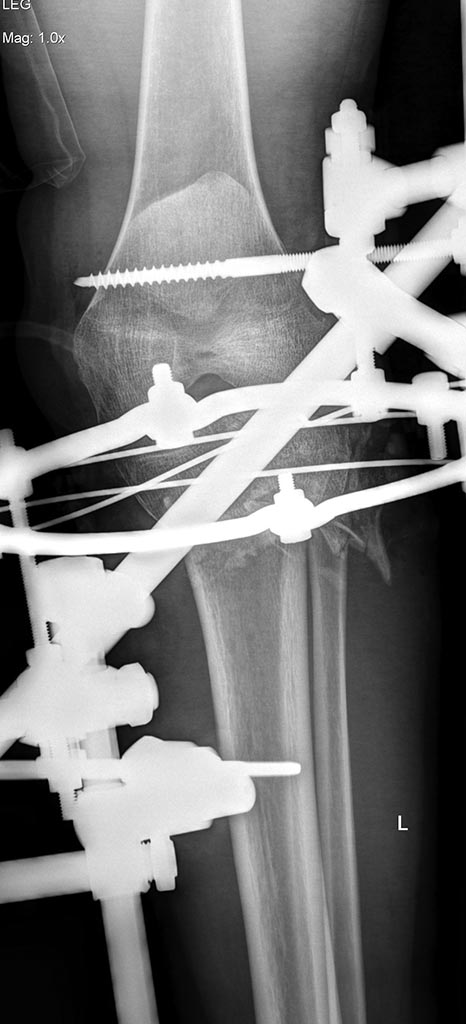

Уважаемые коллеги! Поступила пациентка после получения травмы в

результате столкновения с препятствием.

Открытые (3a-b) оскольчатые внутрисуставные переломы проксимального

отдела обеих костей правой и левой голени. (см. снимки)

При поступлении выполнено: ПХО открытых перелом костей правой и левой

голени, фиксация в аппаратах; фиксация перелома левой бедренной кости в

аппарате; иммобилизация левого предплечья лонгетой. Планируем: при